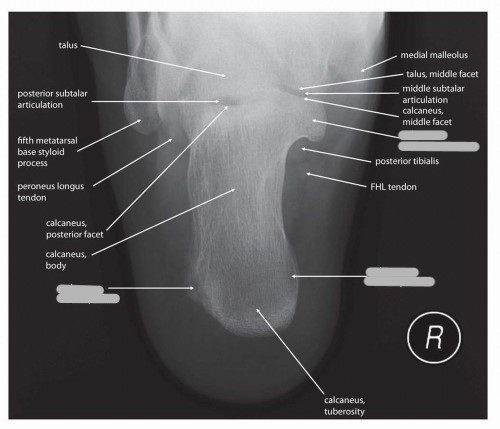

Label the 3 surfaces of the talus that articulate with the calcaneus

What is another name for the talocalcaneal joint?

subtalar joint

Explain the location and function of the sinus tarsi

an opening on the lateral aspect of the foot between the talus and calcaneus; allows ligaments of the foot to pass through